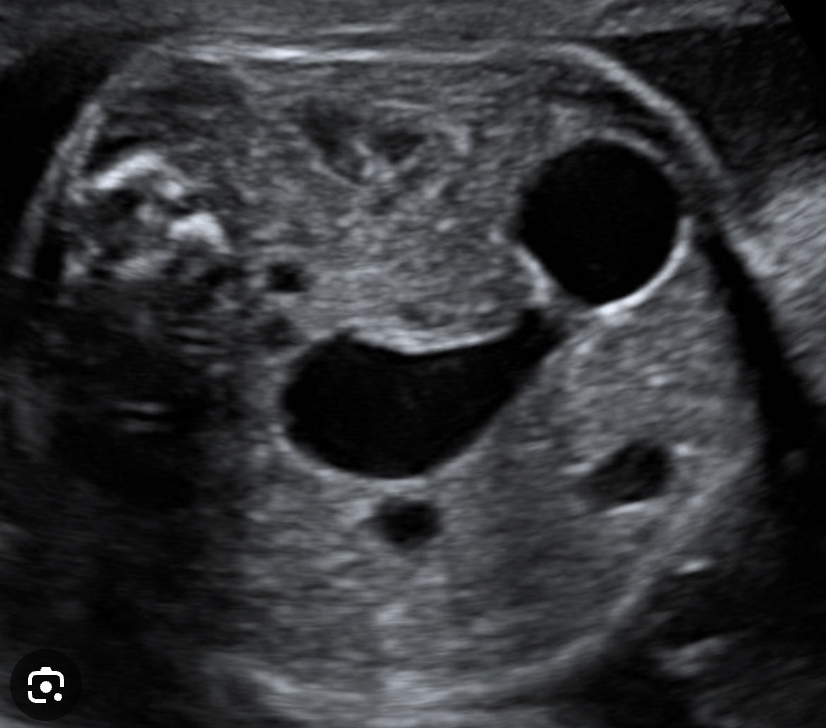

What is the condition?

Duodenal atresia

Aka: Double bubble sign